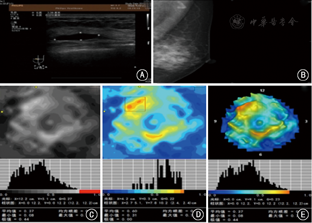

电阻抗断层扫描仪MEIK设备,主要由一主体机、256电极组成的电极面板和一远端电极组成;图1示EIT技术检测患者双侧乳腺影像的各种数据信息,从患者基本信息,影像深度、电导率异常区域、电导率曲线、电导率数据值及双侧电导率分布差异来解析受检者乳腺图像;图2示1例70岁女性乳腺癌患者术前影像资料对比:A: 超声示左乳外上一形态不规则、低回声肿块,边界不清,内可见丰富血流信号,B: 钼靶侧斜位示左乳外上可见类结节影,边缘欠光整,其内可见粗大钙化灶,C~E: MEIK黑白、彩色及三维图像示左乳外上一椭圆形高电导率区,大小2.7 cm×2.4 cm,中心区域最高电导率达1.04,周围组织结构受压;图3示1例44岁女性乳腺纤维腺瘤患者术前影像资料对比:A: 超声示左乳9:00~10:00点方向低回声,大小3.1 cm×0.6 cm,边界清,内回声均匀,未见血流信号;B: 钼靶侧斜位示左乳不均匀致密性腺体,乳腺增生,可见良性钙化;C~E: MEIK黑白、彩色及三维图像示左乳10:00点方向一片状高电导率区,中心区域电导率达0.77,周围组织呈超阻抗区,未见明显受压。